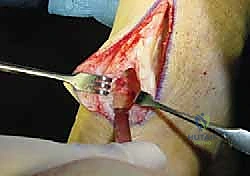

2. الشق الجراحي الدقيق (Incision)

يقوم الدكتور هطيف بعمل شق جراحي طولي دقيق في الجزء الخلفي من الكاحل. بفضل خبرته في الجراحة الميكروسكوبية، يتم التعامل مع الأنسجة المحيطة بحذر شديد للحفاظ على الأعصاب والأوعية الدموية.

3. استئصال الأنسجة التالفة (Debridement)

هذه خطوة حاسمة. يتم فتح الغلاف المحيط بوتر أخيل وفحص الوتر بدقة. يقوم الجراح بإزالة جميع الأنسجة الندبية، الميتة، والمتكلسة (التي تسبب الألم). في الحالات الشديدة، قد يتم إزالة أكثر من 50% من حجم وتر أخيل الأصلي لأنه لم يعد صالحاً للعمل.

4. عزل وحصاد وتر FHL (Tendon Harvesting)

يتم تحديد مسار وتر FHL الذي يقع أعمق قليلاً من وتر أخيل. يتم فصل الوتر بعناية من نقطة اتصاله السفلية (عند منتصف القدم تقريباً) لضمان الحصول على طول كافٍ للنقل. وتجدر الإشارة هنا إلى أن قطع هذا الوتر لا يؤثر بشكل ملحوظ على وظيفة المشي أو حركة إصبع القدم الكبير، حيث تتولى عضلات أخرى هذه المهمة بكفاءة.

5. نقل وتثبيت الوتر (Tenodesis & Fixation)

هنا يتجلى الفن الجراحي. يتم حفر نفق صغير جداً في عظم الكعب (Calcaneus). يُسحب وتر FHL القوي ويُزرع داخل هذا النفق العظمي. يتم تثبيته باستخدام مسمار تداخلي حيوي (Bio-interference screw) يندمج مع العظم بمرور الوقت، مما يوفر تثبيتاً صخرياً قوياً.

بالإضافة إلى ذلك، يقوم الدكتور هطيف بخياطة ما تبقى من وتر FHL مع وتر أخيل الأصلي (Side-to-side anastomosis) لتعزيز القوة الميكانيكية المزدوجة.